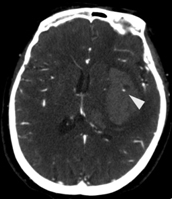

AVC hemorrágico

Sinal de ponto na angiotomografia (ponta da seta), indicando a presença de material de contraste hiperdenso no leito do hematoma na tomografia computadorizada (TC) após a injeção, correlacionou-se com maior risco de expansão subsequente do hematoma

Arquivos de casos pessoais do Foothills Medical Center; usados com permissão